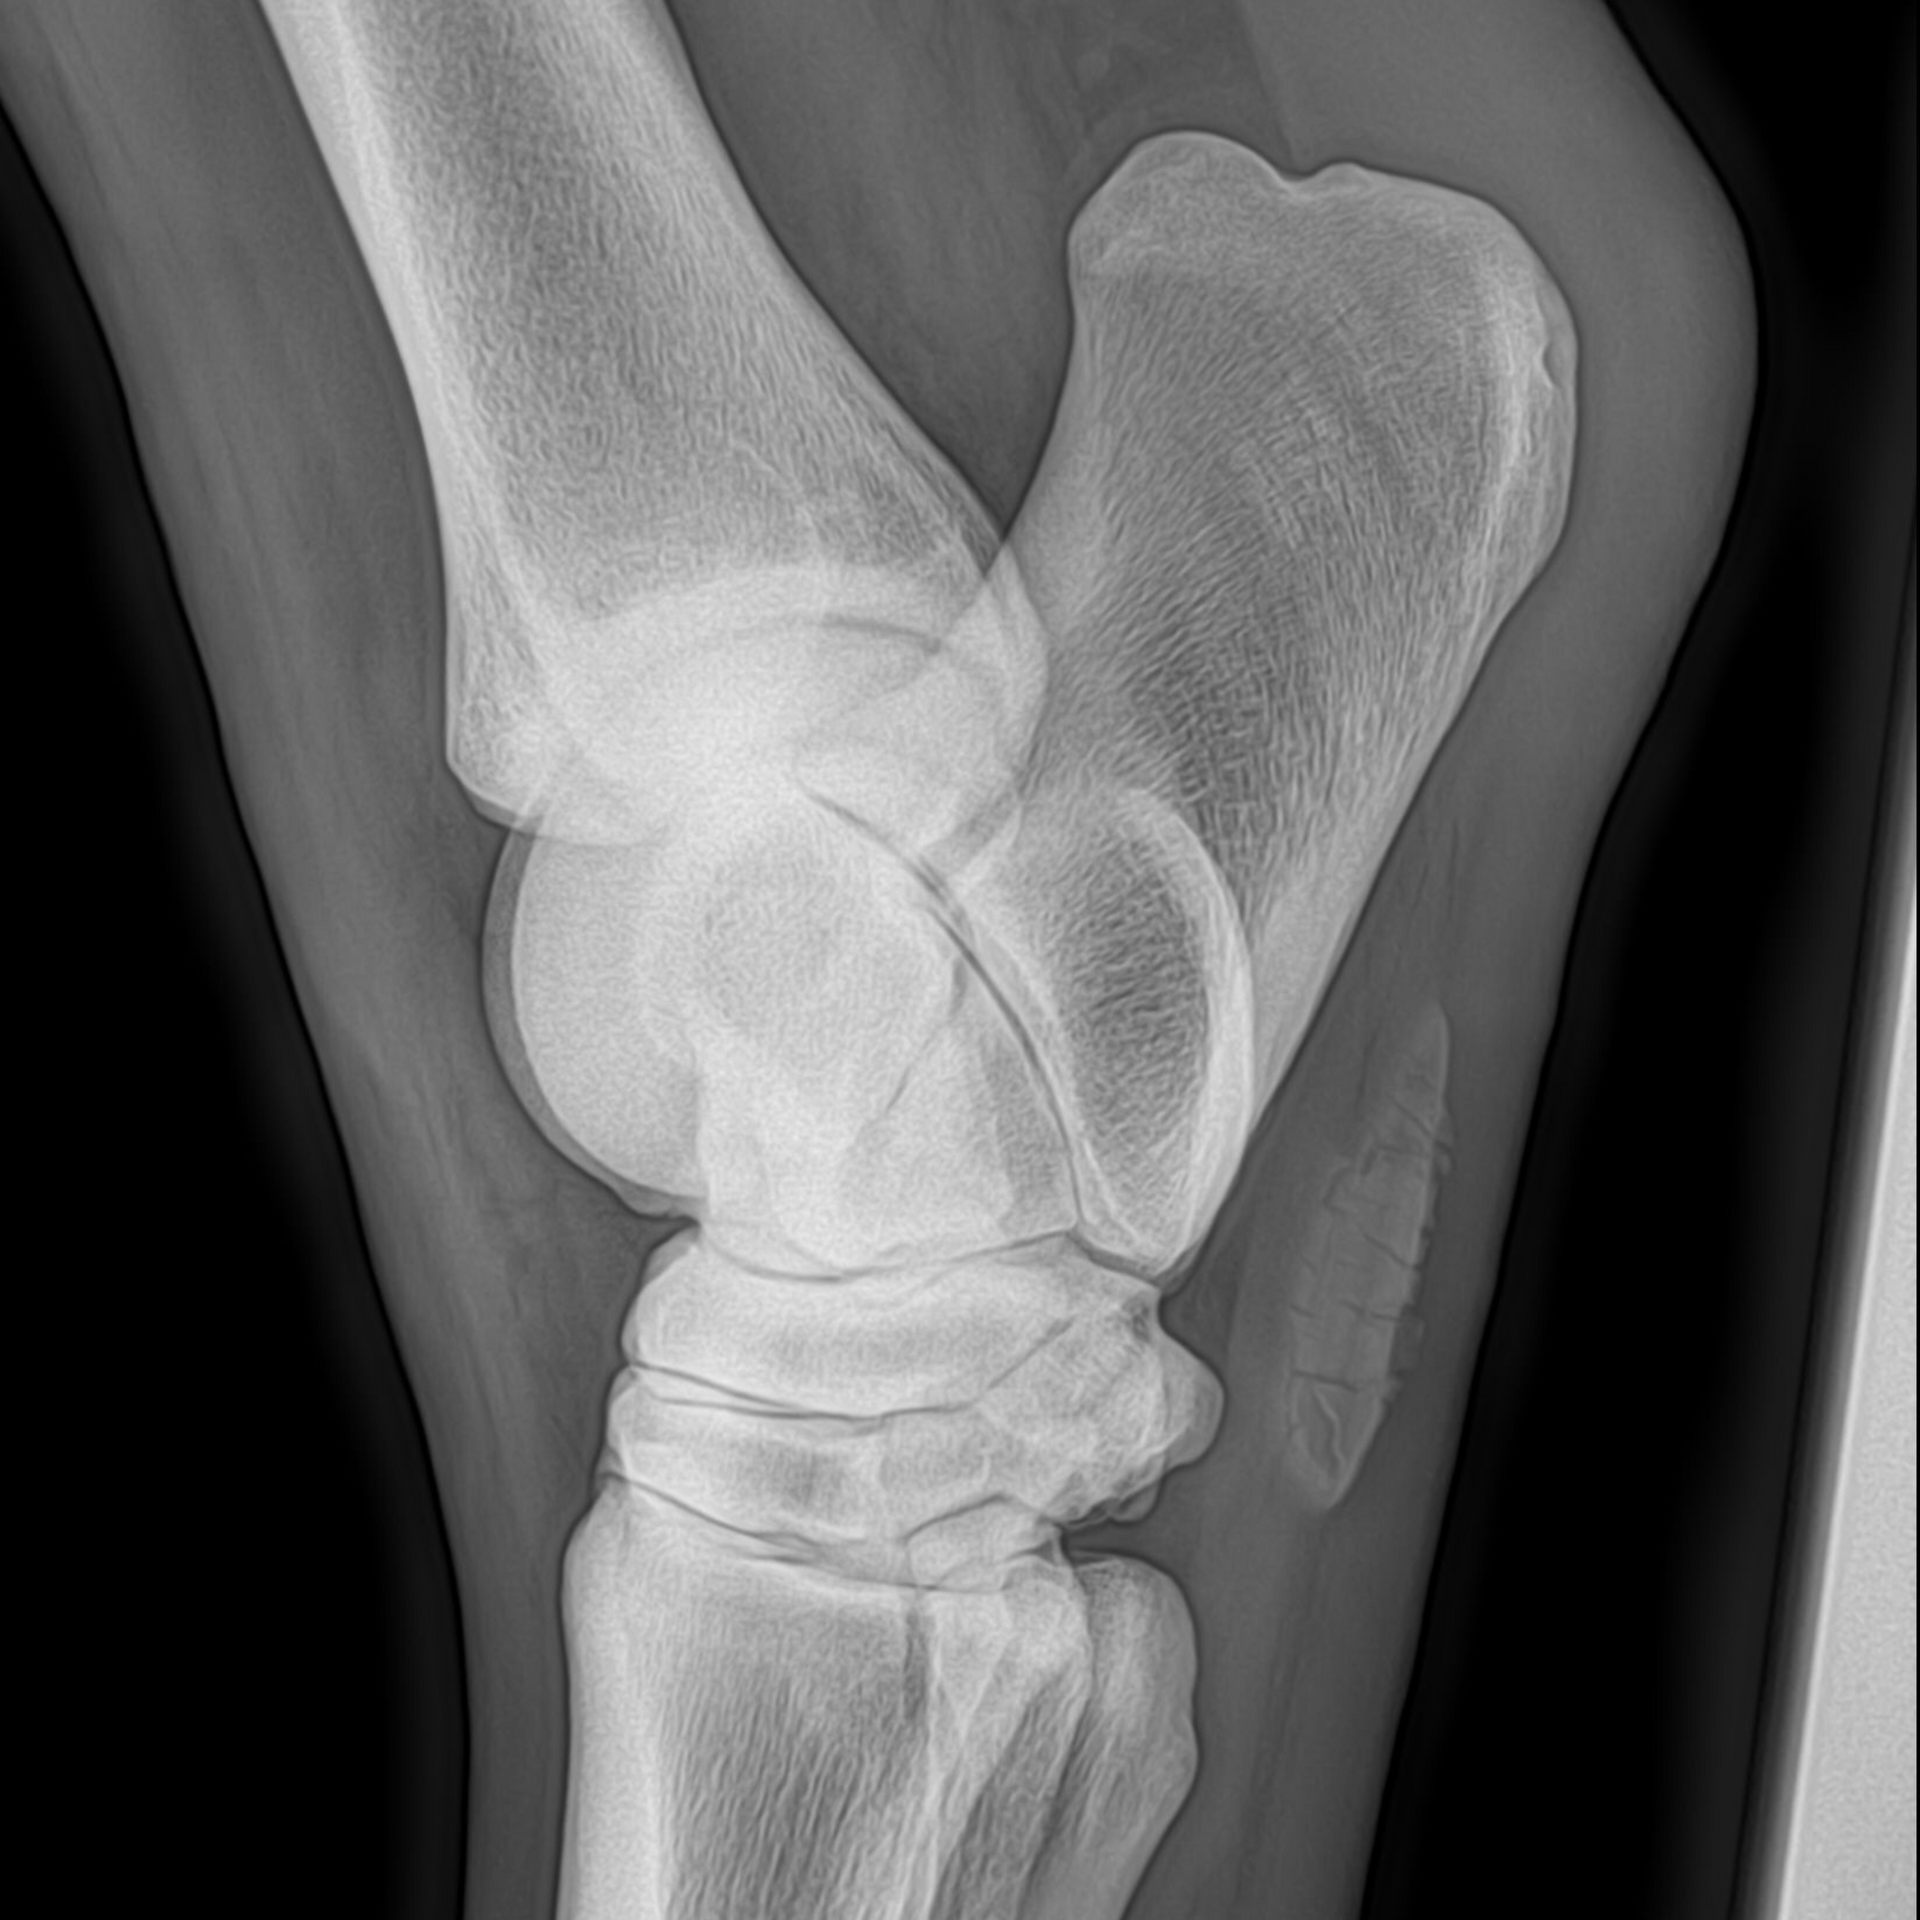

Röntgenologie

Met röntgenfoto's krijgen we een duidelijk beeld van botstructuren. De apparatuur gaat vanaf maart 2026 mee in de auto en is dan dus direct beschikbaar voor gebruik.